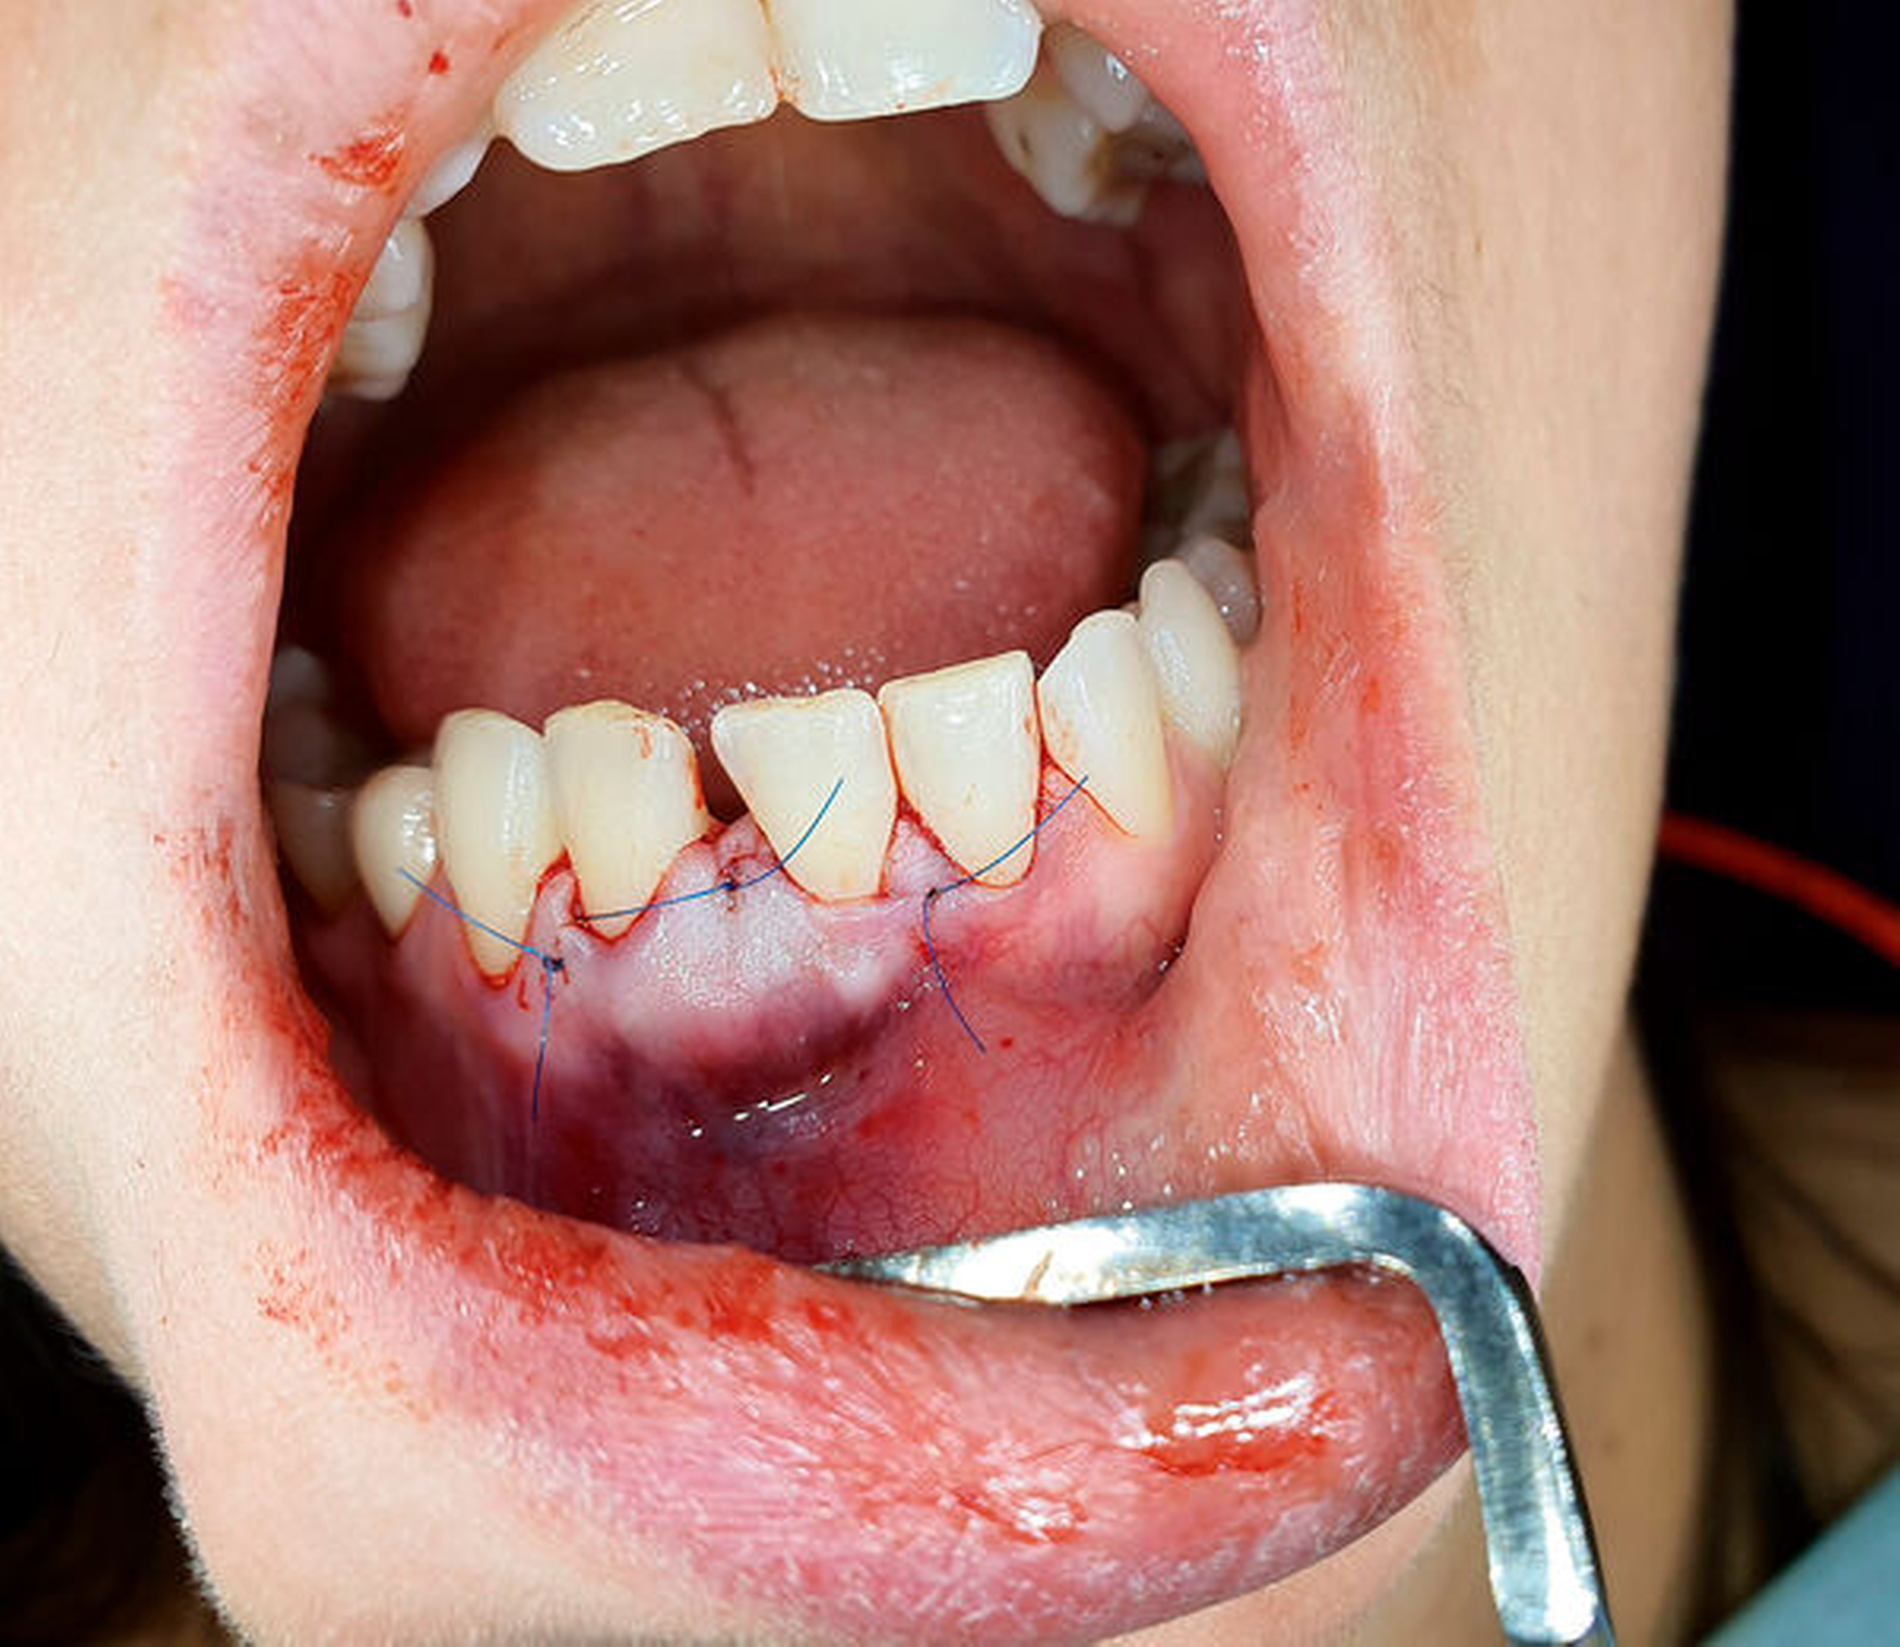

Danach erfolgte die Adaptation der Wundränder mit Papillennähten (Abbildung 5).

Die pathologische Untersuchung ergab ein ausgeprägtes myxoid-kollagenfaserreiches Stroma in einem mesenchymalen Proliferat. Daher konnte die Diagnose eines odontogenen Myxoms getroffen werden. Die postoperative Medikation bestand aus einem nichtsteroidalen Antiphlogistikum (Ibuprofen 600 mg; alle 6 h für den ersten Tag). Am Folgetag stellte sich die Patientin mit einer minimalen Schwellung vor, die Nähte wurden nach einer Woche entfernt. Nach Aufklärung über die Rezidivraten odontogener Myxome wurden mit der Patientin regelmäßige Nachsorgetermine vereinbart.